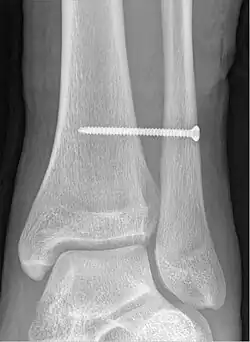

Syndesmotic screw

A syndesmotic screw is a metal screw designed to replace the syndesmosis of the human body, usually temporarily. If the syndosmosis is torn apart as result of bone fracture, surgeons will sometimes fix the relevant bones together with a syndesmotic screw, temporarily replacing the normal articulation.

A syndesmotic screw designed to replace the inferior tibiofibular articulation that fix the tibia and fibula together at the lower joint, is 5–6 cm long and made of a stainless, solid metal.

The screw may inhibit normal movement of the bones and, thereby, the corresponding joint(s). When the natural articulation is healed, the screw may be removed.[1]